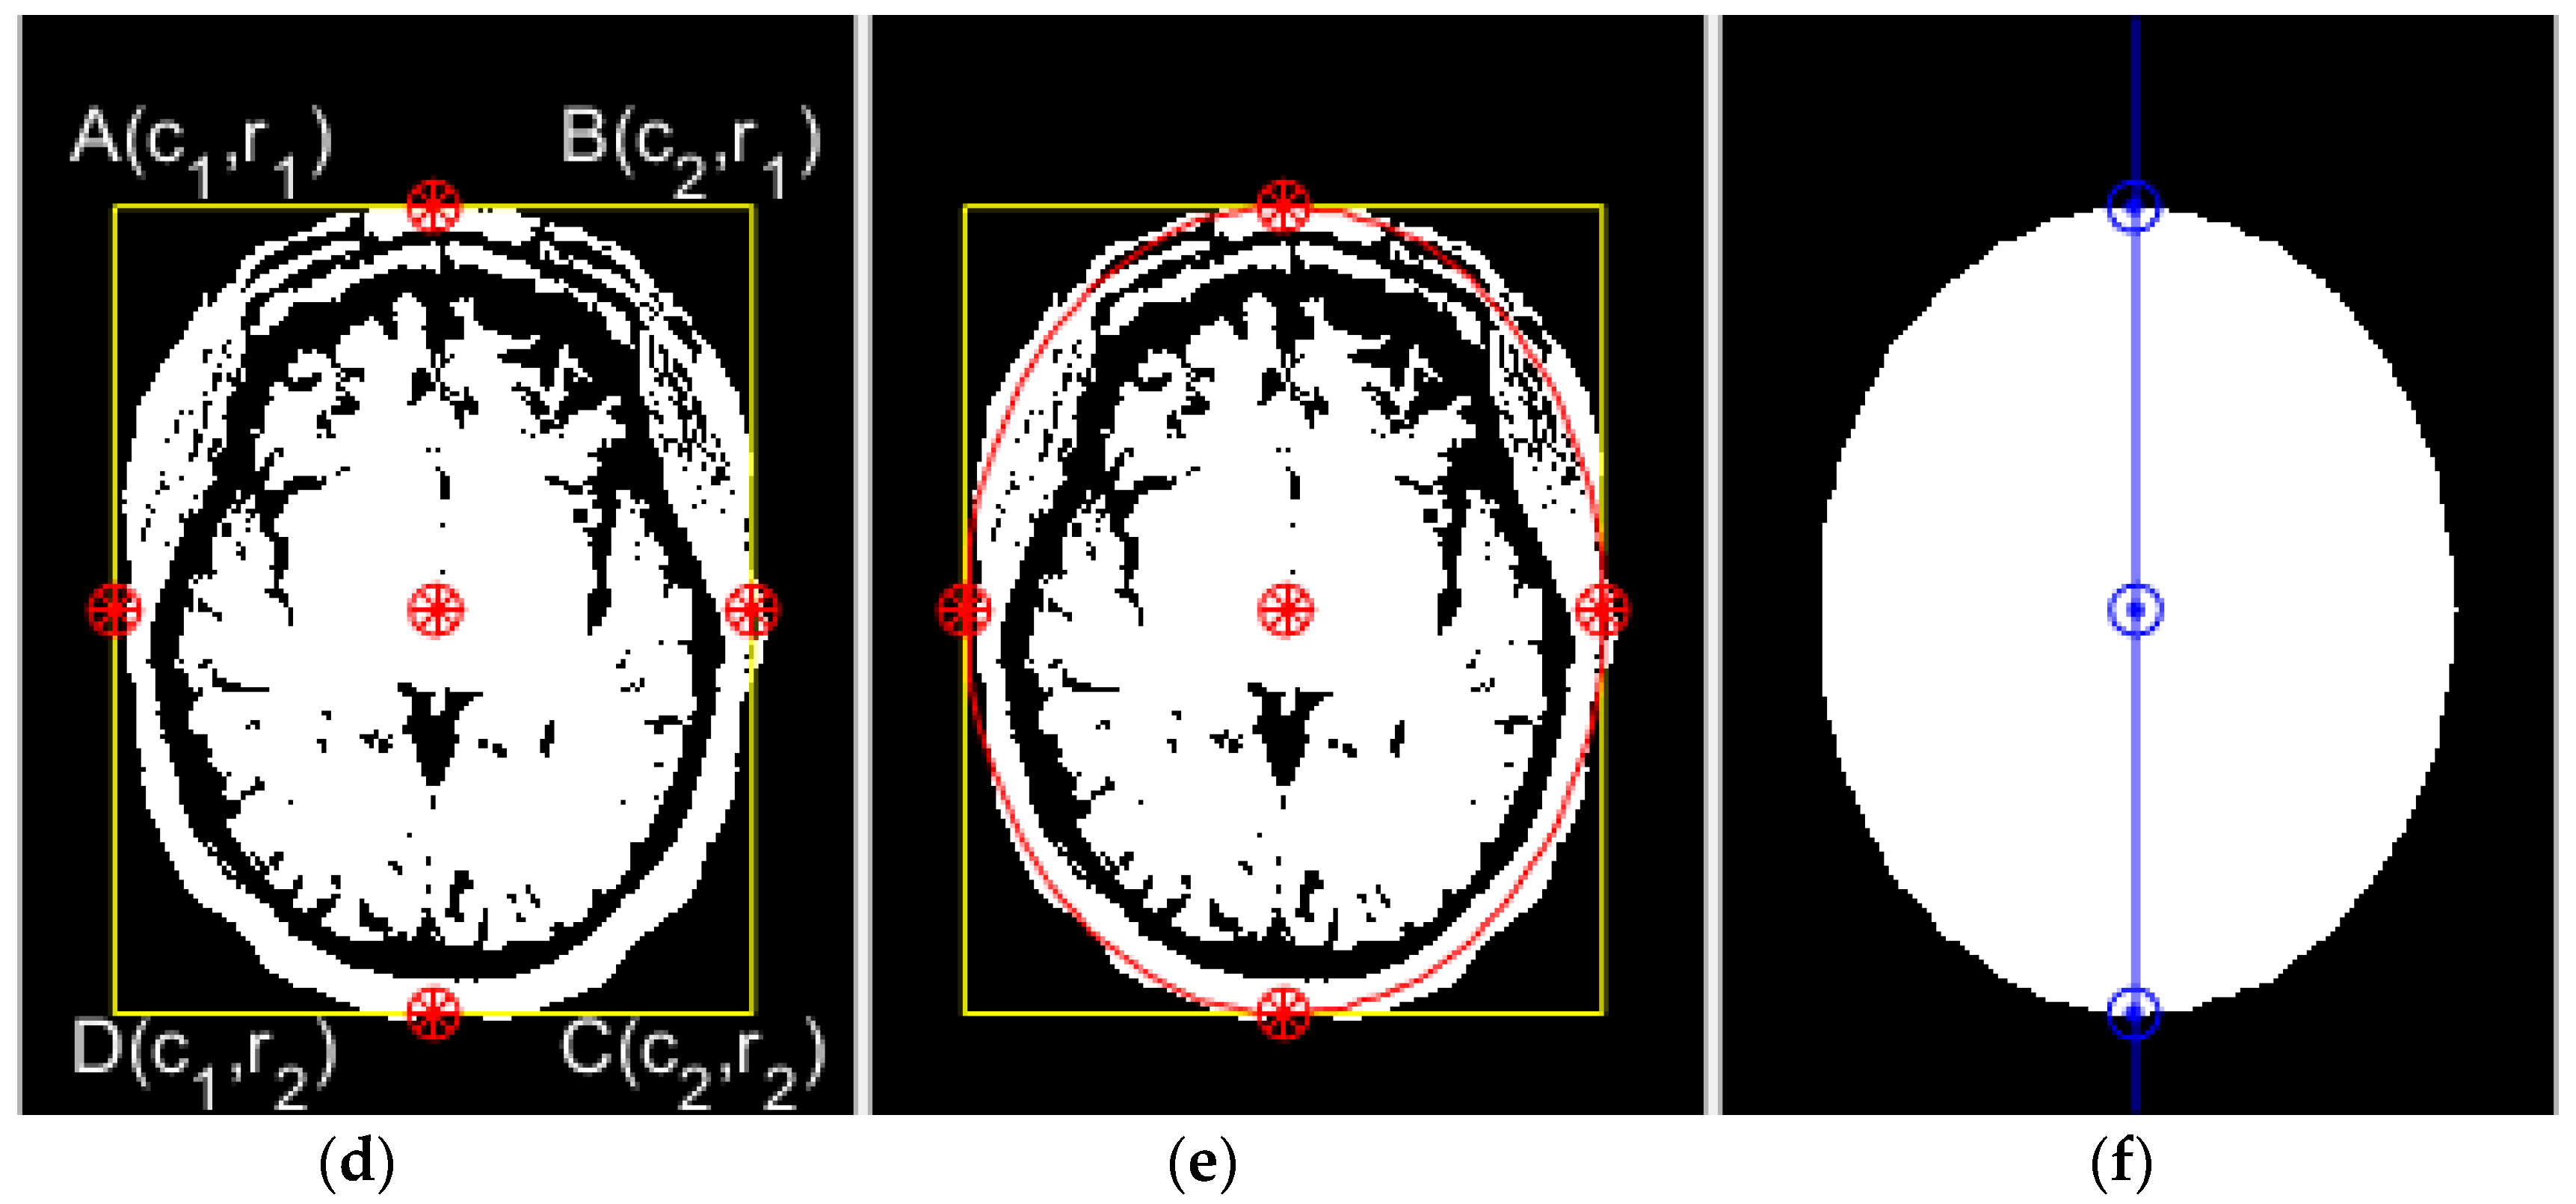

2.2.2. Principal Component Analysis